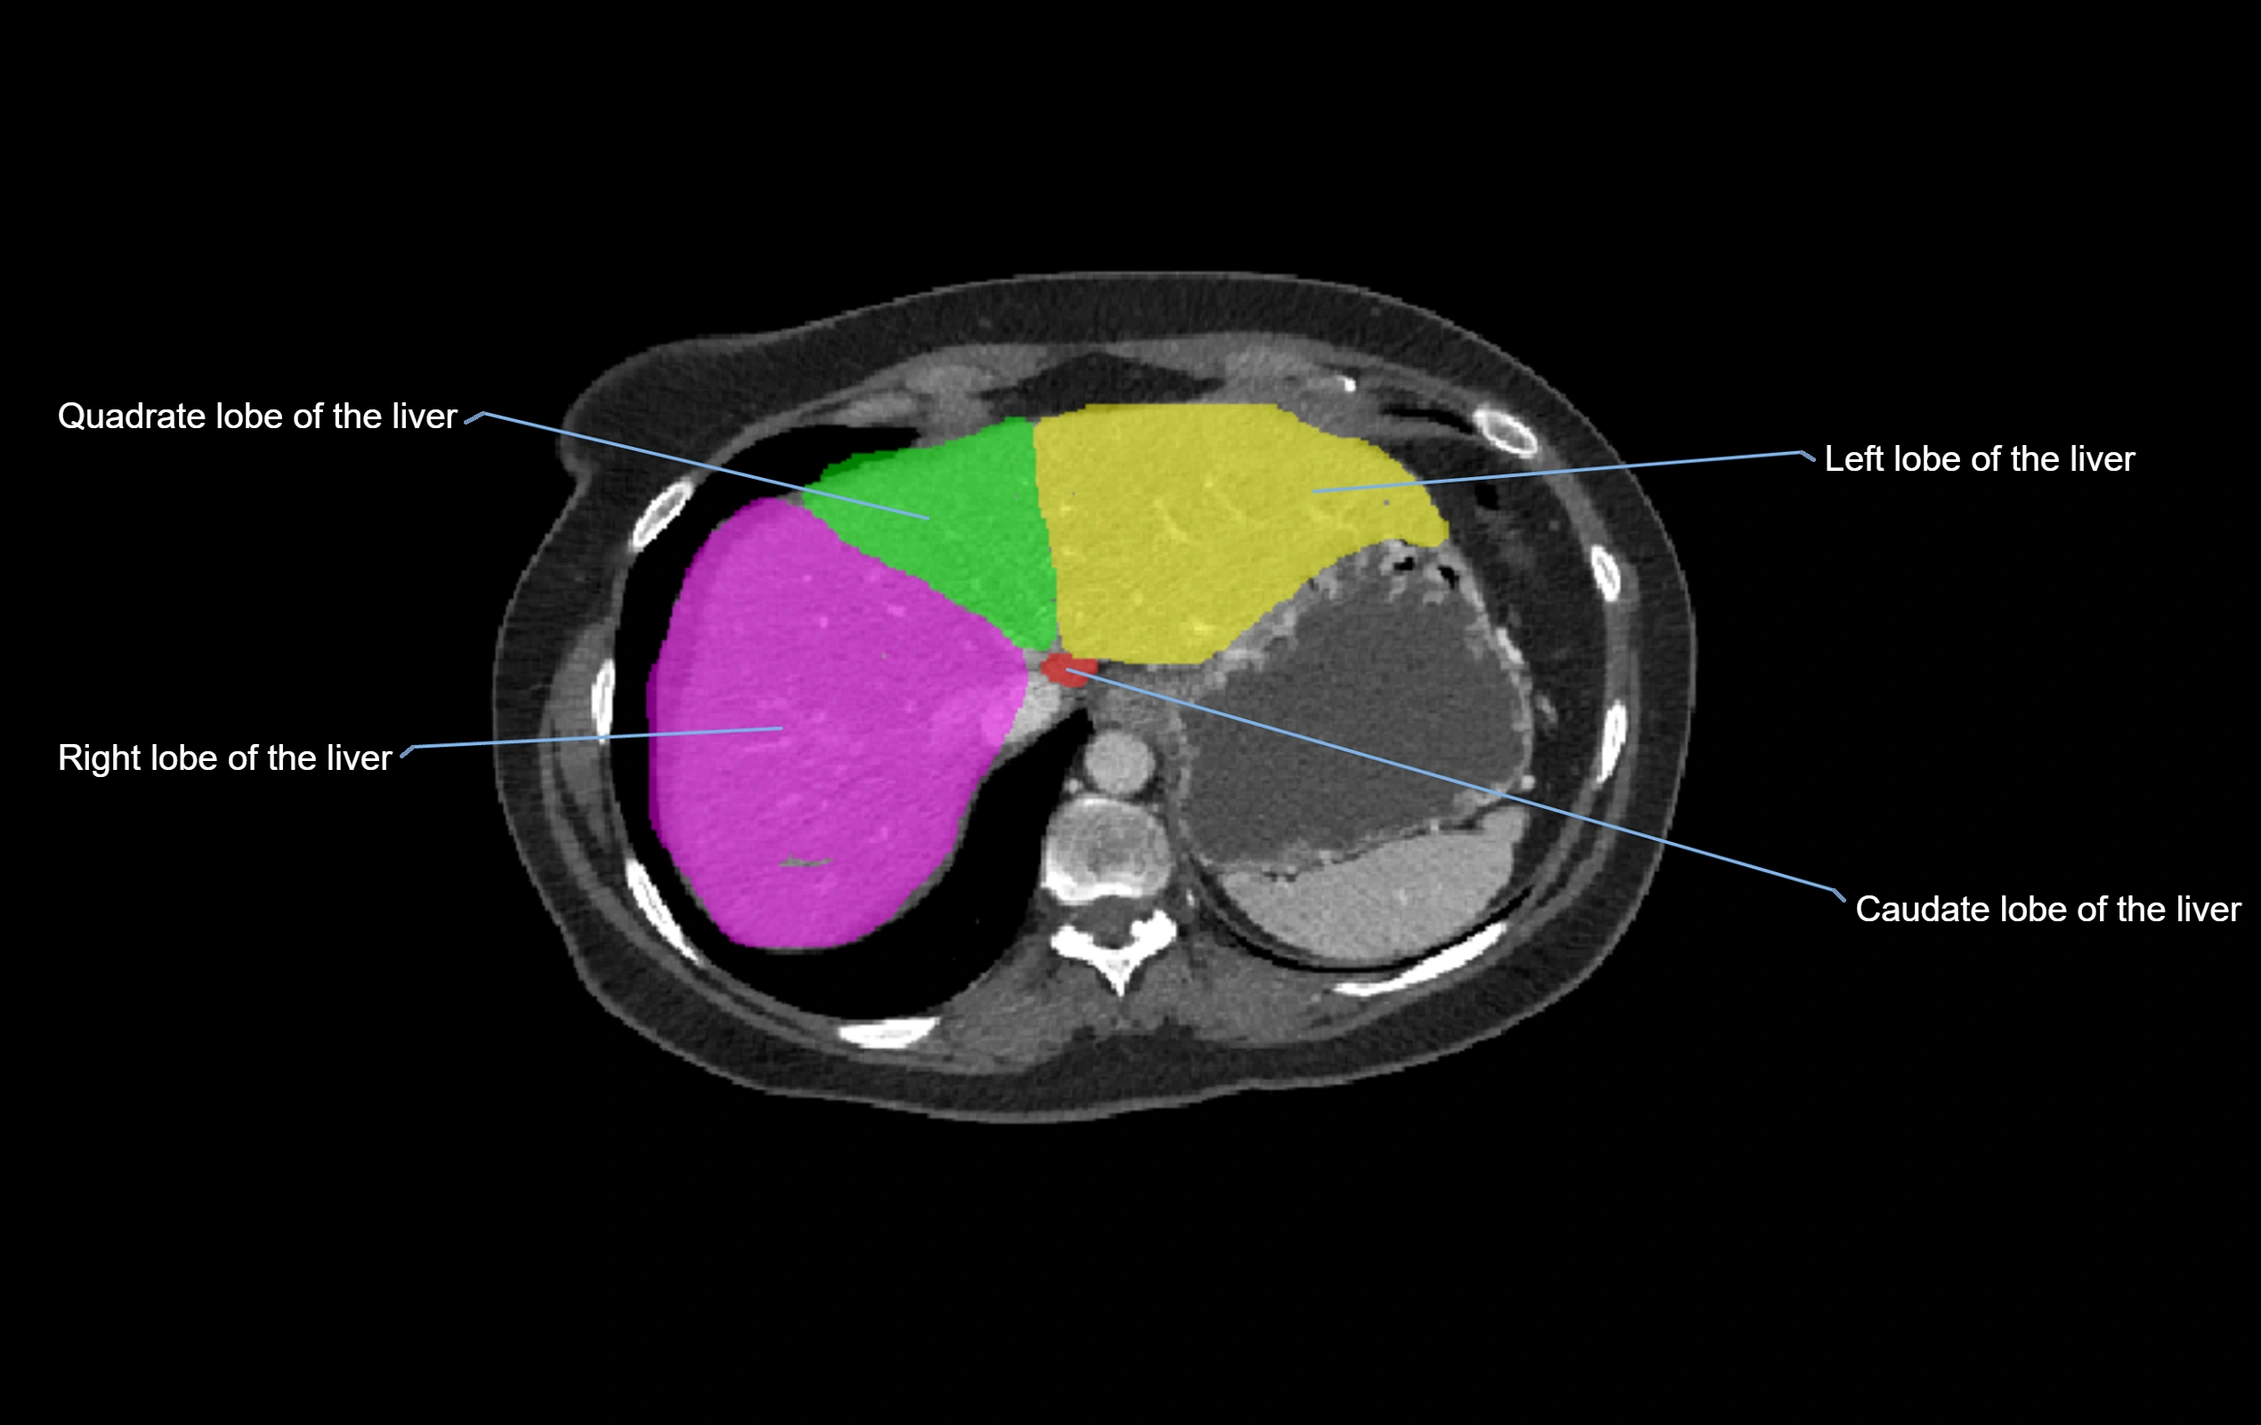

Caudate lobe of liver

The caudate lobe of the liver is a distinct anatomical subdivision of the liver, designated as segment I in Couinaud’s classification. It lies on the posterior surface of the liver, between the fissure for the ligamentum venosum (left boundary) and the groove for the inferior vena cava (IVC) (right boundary). Superiorly, it is related to the posterior liver surface, and inferiorly it is separated from the left lobe by the porta hepatis.

The caudate lobe is unique because it receives dual portal venous and arterial inflow from both the right and left portal veins and hepatic arteries. It also has independent venous drainage directly into the IVC via multiple small hepatic veins, unlike other lobes that drain through the three main hepatic veins.

This anatomical autonomy makes the caudate lobe especially significant in liver surgery, transplantation, and hepatic venous outflow obstruction syndromes (e.g., Budd–Chiari syndrome). Enlargement of the caudate lobe is a characteristic imaging feature in chronic liver disease and cirrhosis.

CT Appearance

CT Pre-Contrast:

• Caudate lobe appears as a soft-tissue density, isodense to the rest of the liver

• Enlargement may be appreciated in cirrhosis or Budd–Chiari syndrome

CT Post-Contrast:

• Homogeneous enhancement in the portal venous phase, similar to rest of liver

• Independent venous drainage into the IVC may be visualized

CT Image

image